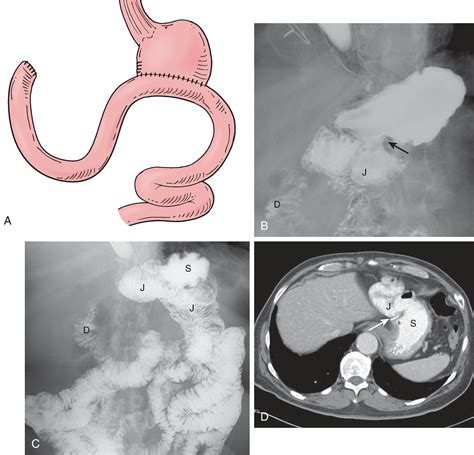

Billroth 2 surgery, also known as distal gastrectomy with gastrojejunostomy, involves the removal of the distal portion of the stomach and the creation of a loop of the jejunum to connect the remaining stomach to the small intestine. This procedure is often performed for conditions similar to those treated with Billroth 1, but it is more commonly used when the duodenum is not suitable for anastomosis.